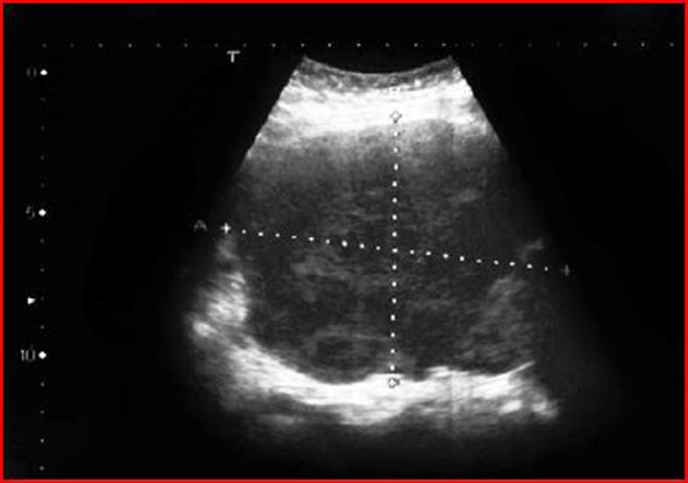

On the other hand, the literature reports cases of ovarian Burkitt lymphoma that were treated immediately by surgery, precisely because the diagnosis of lymphoma was not suspected. This is the case described in Szu-Ching Lu et al [10] who describe the appearance of ovarian Burkitt’s lymphoma in a 50-year-old woman. Unfortunately, the woman does not present with the common systemic symptoms of lymphoma such as fever, night sweats, nausea, vomiting or bladder symptoms. His Pap test was normal and on physical examination, as in the cases described previously, a pelvic mass of the size of approximately 20 weeks of gestation was revealed. The high resolution trans-vaginal ultrasound examination revealed a large and homogeneous abdominal mass measuring 10.8 x 8.7 cm extending from the uterus to the left ovary and the presence of a minimal content of free liquid (Figure17-18 ). Power-Doppler ultrasound showed no vascularity in the mass. All blood tests, including tumor markers, were normal before surgery.

Figure 17: Trans-abdominal ultrasound showing a large irregularly shaped echogenic pelvic mass. The mass measures 10.8 x 8.7 cm.

Figure 18: Trans vaginal ultrasound showing a large pelvic mass, extending from the right anterior wall of the uterus, with homogeneous echogenicity and some small anechoic areas within the mass.